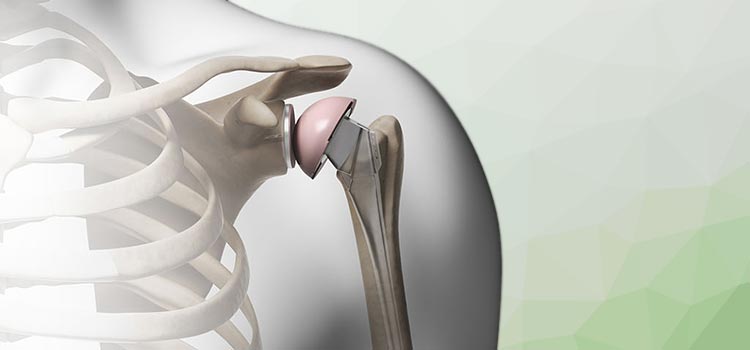

Artroplastia / Prótese de Ombro

A artroplastia de ombro consiste na substituição parcial ou total da articulação do ombro por uma prótese. O principal objetivo do procedimento cirúrgico é devolver qualidade de vida ao paciente, diminuindo a dor.